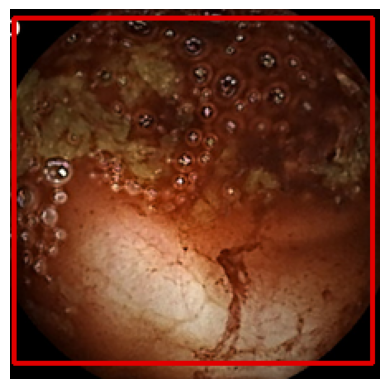

The final results are summarized in Table I. Test dataset 1 mainly contained images with small bleeding patches, yielding a classification accuracy of around 50%. Fig. 3 illustrates one exemplary prediction from the test dataset.

Refer to caption

(a) Bounding Box

(b) Image mask

(c) CAM Plot

Figure 3: Result on test dataset 1